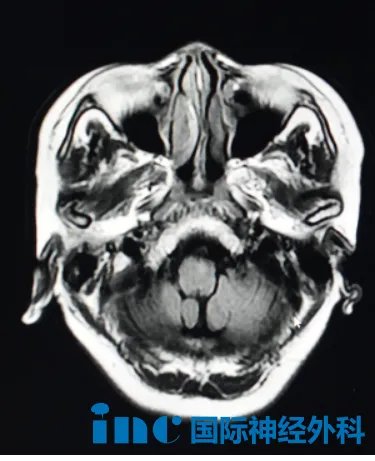

从右腿无力、“脚踩棉花”开始,57岁赵女士的安稳生活被彻底打破。初诊发现桥脑病变与小脑脂肪瘤时,医生建议“随访观察”。短短6个月,她的身体迅速被疾病侵蚀:右腿跛行,右臂痉挛,曾经灵巧的右手连基本活动都变得异常困难。复查,医生考虑桥脑腹侧、中脑脚间窝胶质瘤可能,不建议手术,建议放化疗。这一刻,她和家人心中充满了无力感与疑问:到底是什么病?真的要盲放、盲化吗?

然而,巴教授的评估带来了一个让她又惊又喜的转折:中脑位置的病灶不是肿瘤,更像炎症性疾病。他建议进一步脑部核磁检查以观察变化。至于小脑脂肪瘤,巴教授则认为无需处理,定期观察即可。一个截然不同的诊断,为这个家庭也指明了新的方向。